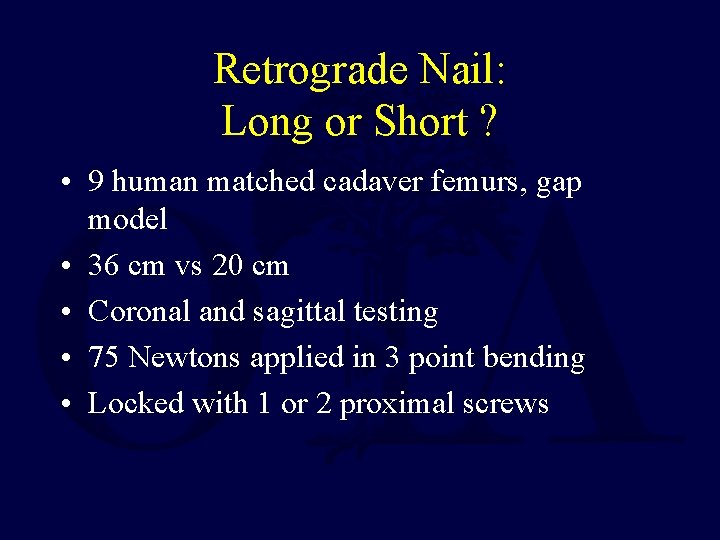

Retrograde Nail: Long or Short ? • 9 human matched cadaver femurs, gap model • 36 cm vs 20 cm • Coronal and sagittal testing • 75 Newtons applied in 3 point bending • Locked with 1 or 2 proximal screws